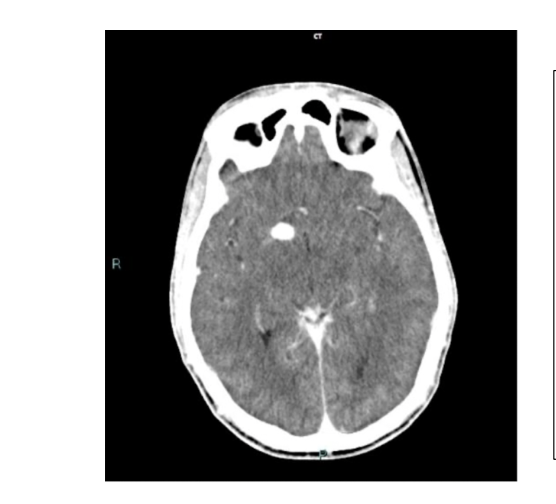

What is the pathology?

Skull fracture along lambdoid suture line.

Sits along the suture and the regular suture pattern is abnormal.

Best seen on non-contrast brain bone window.